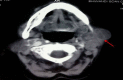

Primary Tubercular Sialadenitis - A Diagnostic Dilemma

Introduction: Involvement of the salivary glands in tuberculosis is rare, even in countries where tuberculosis is endemic. It can occur by systemic dissemination from a distant focus or, less commonly, as primary involvement. This article focuses on its myriad clinical presentations that pose a diagnostic challenge to the clinician. We discuss the schema of investigations required to confirm the diagnosis and the limitations faced in the low-cost setting of a developing country.

Results: Seven patients were treated over a 2-year period. The most common mode of presentation was a painless mass of the involved gland in four patients. One patient each presented with chronic non-obstructive sialadenitis, sialolithiasis, and acute suppurative sialadenitis. Fine needle aspiration cytology was diagnostic in five out of seven cases (71.4%), while mycobacterial culture was positive in two patients (28.6%). In one patient, a diagnosis could only be reached on histopathological examination of the resected gland.

Conclusion: We recommend cytology studies, acid-fast bacilli staining, and mycobacterial culture as the initial investigation on the aspirate in suspected patients, while polymerase chain reaction should be reserved for negative cases. A high index of suspicion, early diagnosis, and timely institution of anti-tuberculosis treatment is essential for establishing cure. The role of surgery in diagnosed cases of tuberculosis is limited.